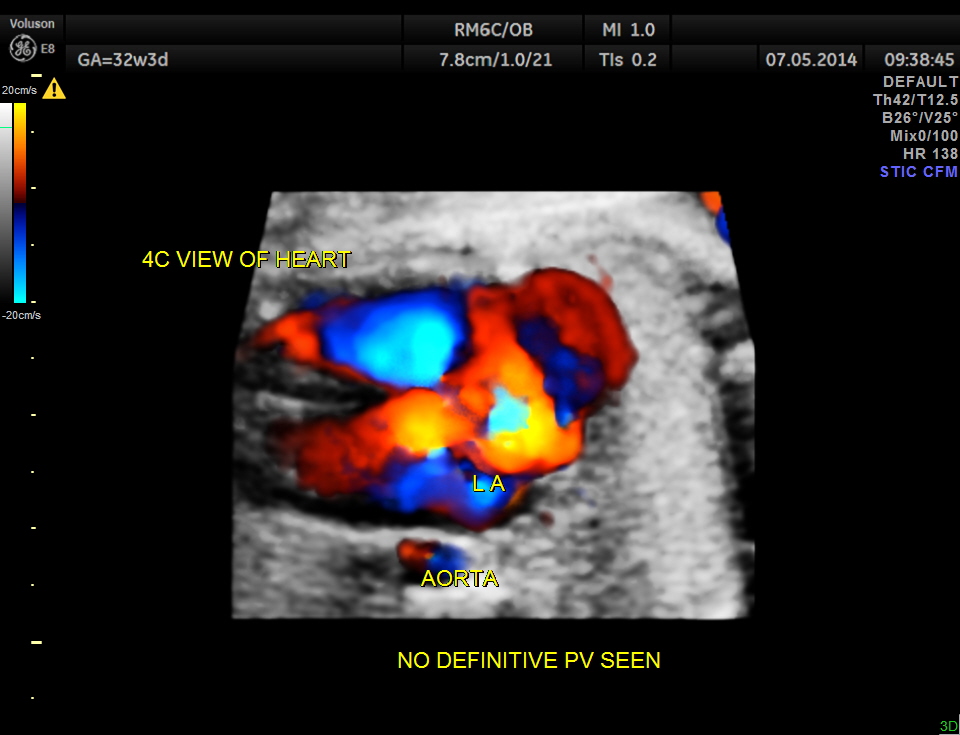

The following is a glass body imaging with a low flow setting. No pulmonary vein draining into LA could be made out.

A transverse vessel is seen below the left atrium and is not seen to drain into the left atrium.

No definitive pulmonary vein draining into the left atrium could be made out . A common transverse vessel was seen beneath the left atrium . The LA & RA were smaller than the RA. Similarly the Aorta and the aortic arch were smaller than the pulmonary artery and the ductal arch due to the increased flow in the right side.